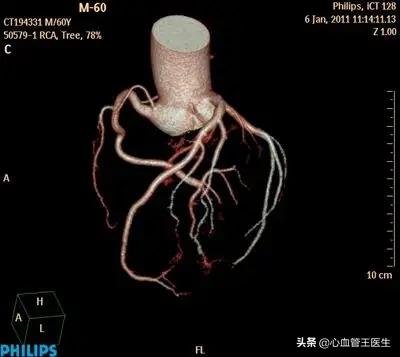

王医生:理论上做心脏CTA和心脏造影检查都能看出来哪根血管堵死了,但是现在高度怀疑得过心肌梗死,且已经出现心衰,所以还是建议直接做造影比较好。因为CT只是一种检查,如果发生血管狭窄,并不能治疗,甚至还得再次心脏造影。这样不但多花钱,而且还遭受两次辐射,受两次造影剂危害。造影一步到位,如相对CT更加准确,如果造影发现问题,还能当时就打通血管,或解决狭窄血管,免遭二次痛苦。

老周住院后,造影检查显示心脏左前方前降支血管中段完全堵塞,且已经有右侧血管的逆向血流,于是我们花费很长时间打通血管,在一定程度上能改善心肌缺血和心功能。